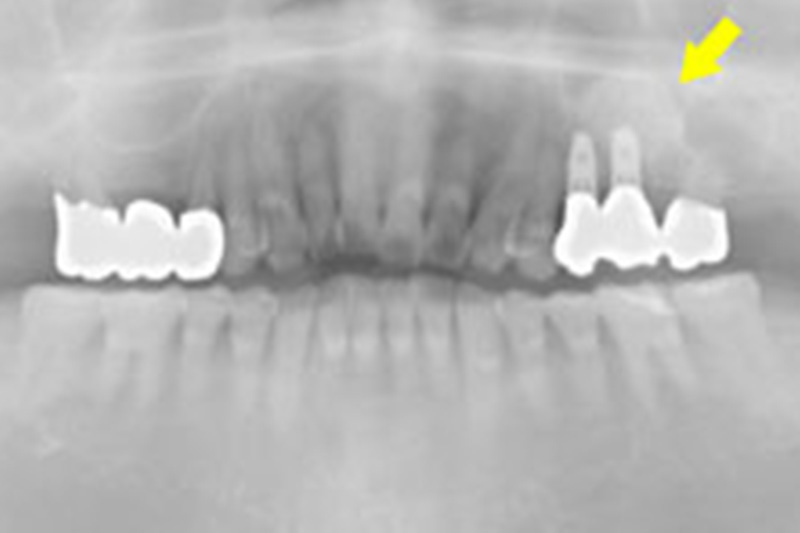

歯科用CTを使用した正確な診断

インプラント治療を成功に導くためには、事前の精密な検査が欠かせません。

当院では歯科用CTを活用し、お口の中を立体的に撮影することで、顎の骨の形態や神経の位置、骨密度まで詳しく把握します。

CTデータをもとに、インプラントを埋入する位置・角度・深さを正確に計画できるため、安全性の高い手術計画が可能になります。

さらに、手術前後の画像を比較することで治療経過を細かく確認でき、より良い結果へとつなげることができます。